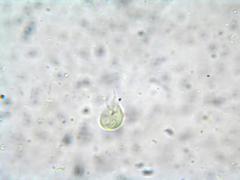

Images from inaturalist.org observations:

We recommend you sign up for this excellent, free service.